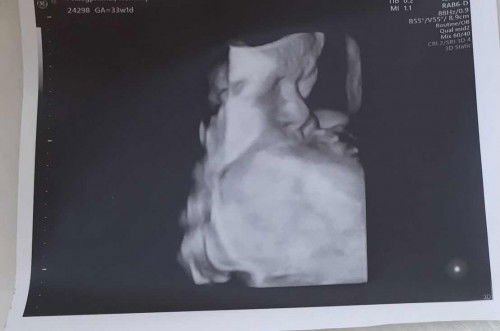

และวันนี้หมอนัดฟังผล ปรากฏว่าเจ้าตัวเล็กเสี่ยงต่ำ แข็งแรงดีป้าหมอบอกที่สำคัญเสียงการเต้นของหัวใจชัดเจนดังดีด้วยนะ😍 แม่ๆคนไหนที่ตรวจดาวน์แล้วทางโรงพยาบาลไม่ได้โทรมาบอกอะไร ให้แม่อุ่นใจไว้เลยนะคะ😊 แม่ๆบ้านไหนตรวจแล้วผลเป็นอย่างไรบ้างคะ?เรา19 วีควันนี้ น้ำหนัก 63 😅#ท้องแรก🥰